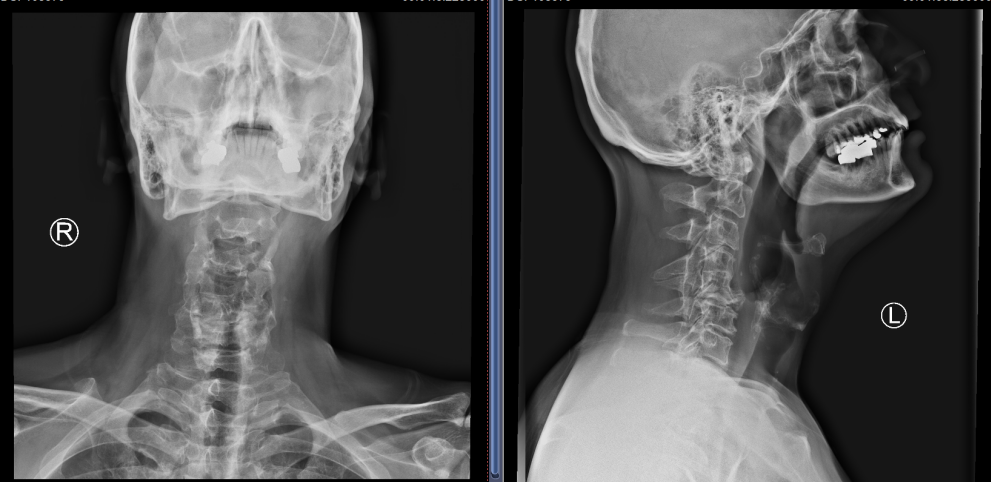

Hester辗转多家医院寻求帮助,其中包括上海著名的三甲医院,都建议手术治疗,他因为担心疗效而犹豫不决。病情的不断加重又使他心急如焚。今年3月初,通过其他专业人士推荐,他前来我院骨科姜为民主任的高级专家门诊就诊。姜主任在仔细询问了他的病史、阅读了他的影像学资料并进行了全面的体格检查后,告诉他共有3个方面的问题:1.颈椎的第四(C4)和第五节椎体(C5)先天发育异常,分节不全;2.C5-6椎间隙倾斜,颈椎侧凸畸形同时伴严重的骨质增生和椎间盘退变。3.磁共振检查显示在C5/6和C6/7水平脊髓严重受压伴脊髓信号明显改变,说明神经损伤已相当严重,尽快手术治疗是唯一的选择。他觉得姜主任对病情的判断与建议与他德国的医生完全一致。“It is a good decision to receive the treatment in the professional hospital which gives me a good feeling at the first sight.”(这是一个正确的决定,我第一眼看到这家医院,就觉得非常的专业)。 在Hester后来的感谢信中写道:Also, the talk with Dr. JiangWeimin and his assistant Dr. Zhao gave me very good feelings. They spent enough time explaining to me with understandable words. It was the professionality of these doctors and the public hospital itself that convinced me to do the next treatment.(姜为民主任和他的助手赵博士与我的交谈非常融洽,他们用通俗易懂的语言耐心地向我解释病情,独墅湖医院是公立医院,专家们所展现出的专业性让我心悦诚服,因此我决定就在这儿接受进一步的治疗)。

患者C4和C5椎体发育异常

C5/6、C6/7椎间盘突出明显,椎管狭窄,脊髓受压严重